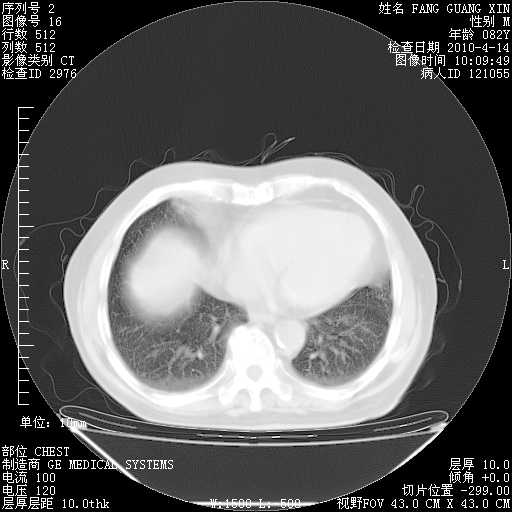

4月14日肺部CT

楼主| 发表于 2010-4-28 16:51 | 显示全部楼层

楼主| 发表于 2010-4-28 16:53 | 显示全部楼层

肺部CT平扫未见异常。